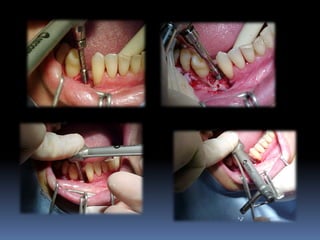

Altura interoclusal

Aumento de coroa clínica

Espaço interproximal modificado

Plataformas regulares ou plataformas

largas?